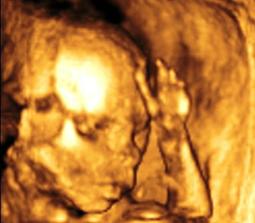

Ako nám to ide...